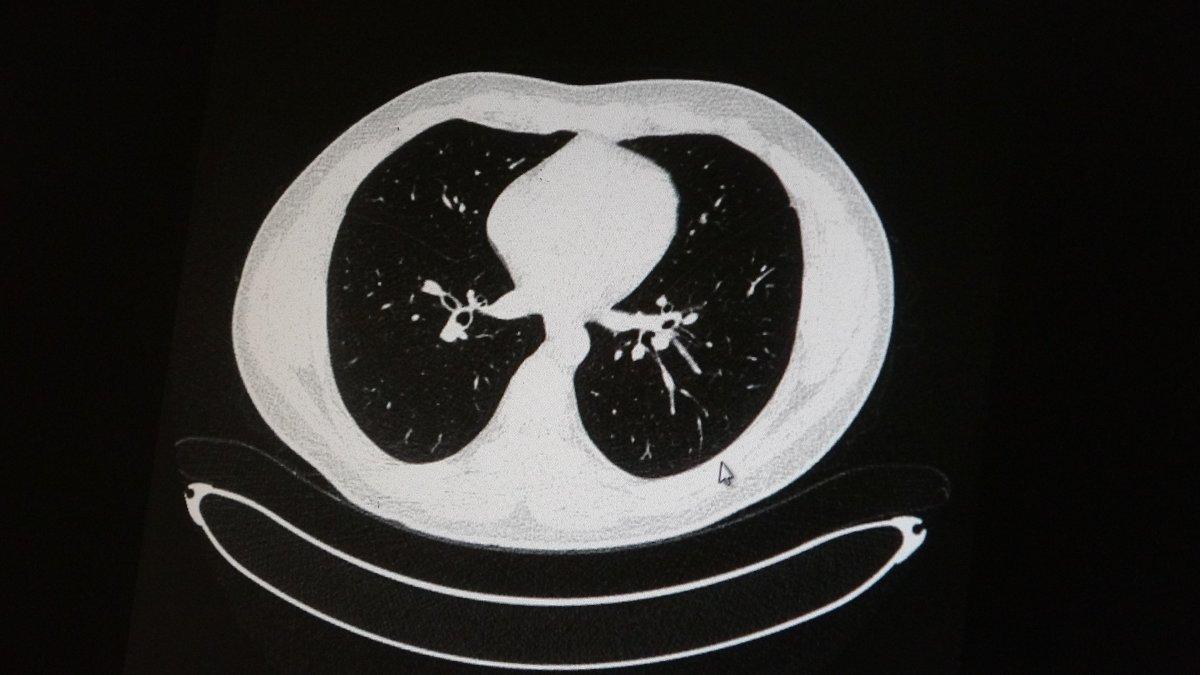

Elazığ'da Göğüs Hastalıkları Uzmanı Dr. Cebrail Azar, genç olduğu halde aşı olmayanlarda hastalığın ağır seyrettiğini ifade ederek "Ben gencim, benim bağışıklık sistemim kuvvetli" diyen genç bir hastanın akciğerlerinde ciddi lekelenmelerin olduğunu ve buna koronavirüs zatürresinin yol açtığını dile getirdi.